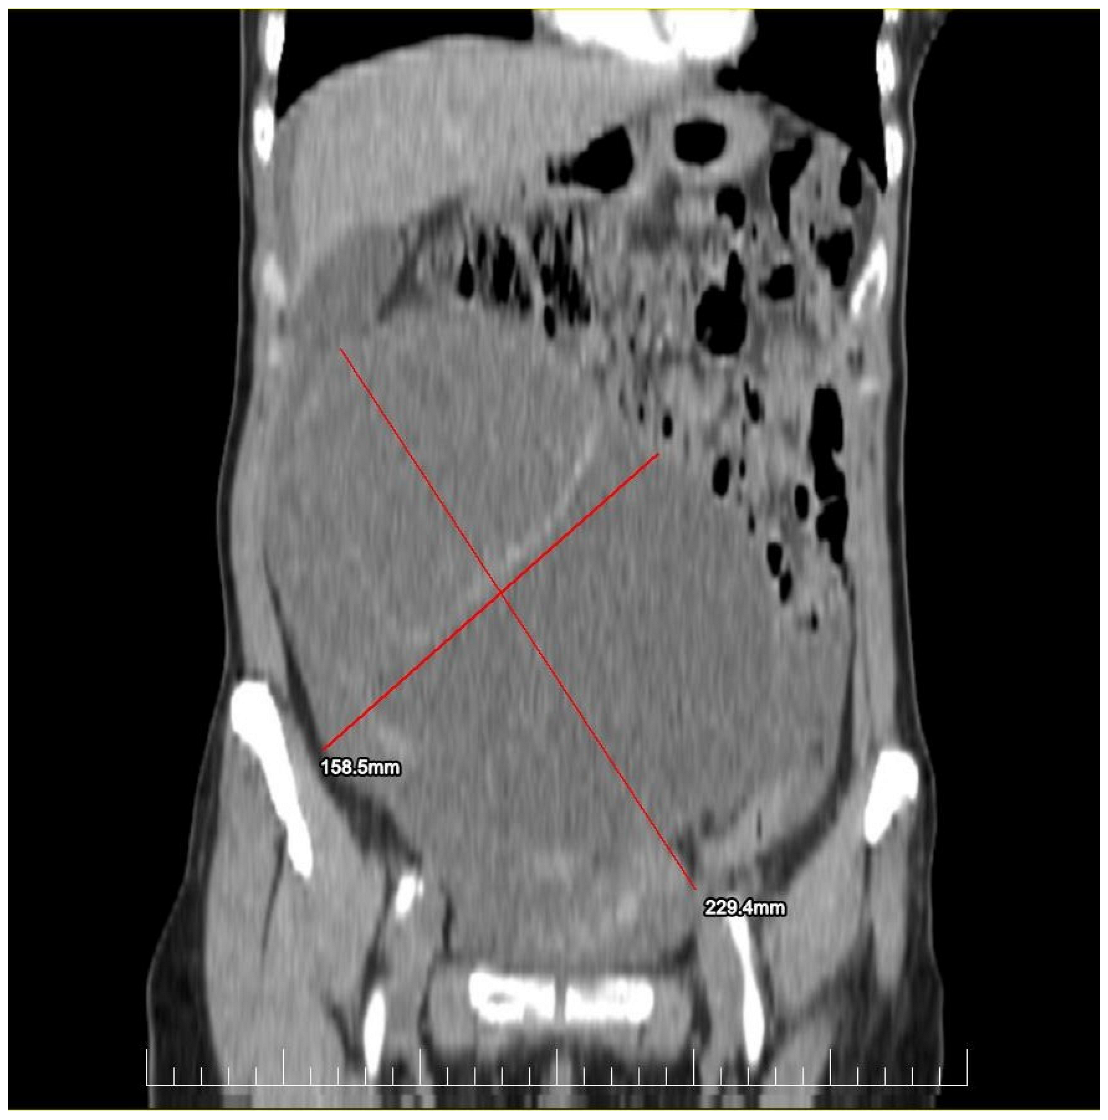

This case report details the presentation, diagnosis, and management of a 44-year-old female who experienced a relapse of colonic cancer with peritoneal carcinomatosis in 2021, two years after the initial diagnosis. The patient exhibited specific symptoms indicative of disease recurrence. In 2019, the patient underwent surgical resection and received adjuvant chemotherapy for colonic cancer. Despite an initial period of remission, in 2021 she presented with symptoms such as abdominal distension, persistent abdominal pain, and changes in bowel habits. Imaging studies, including CT scans, confirmed the presence of peritoneal carcinomatosis, indicating a relapse of colonic cancer along with two suspected tumorous formations localized in the ovaries (Figure 1 and Figure 2). Upon relapse, the patient underwent a thorough diagnostic workup, including imaging studies and tumor marker assessments. Elevated levels of carcinoembryonic antigen (CEA) of 5.44 ng/mL and CA-19-9 of 58 U/mL were observed, supporting the diagnosis of colonic cancer recurrence with peritoneal carcinomatosis.

Figure 1.

Preoperatory coronal view of a Computed Tomography (CT) image presenting a giant ovarian mass.